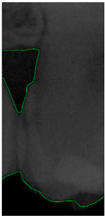

Figure 8.

Image-enhancement results: (a) binarization; (b) mathematical morphology; (c) added green line represents canny; (d) overlap onto the original image.

2.3.5. Canny Edge Detection

Since filtered and binarized images alone cannot enhance the features of dental calculus, this approach does not effectively improve the accuracy of machine learning. Therefore, this study employed edge detection to identify the contours of tooth edges, enhancing the regions of interest and thereby improving the accuracy of machine learning. The canny edge-detection algorithm applies non-maximum suppression to each pixel, retaining pixels with local maximum gradient values, which can produce continuous and accurate edges while demonstrating good resistance to noise. The edge-detection results are represented in green, as shown in Figure 8c. Finally, these results are overlaid back onto the original image, as illustrated in Figure 8d.